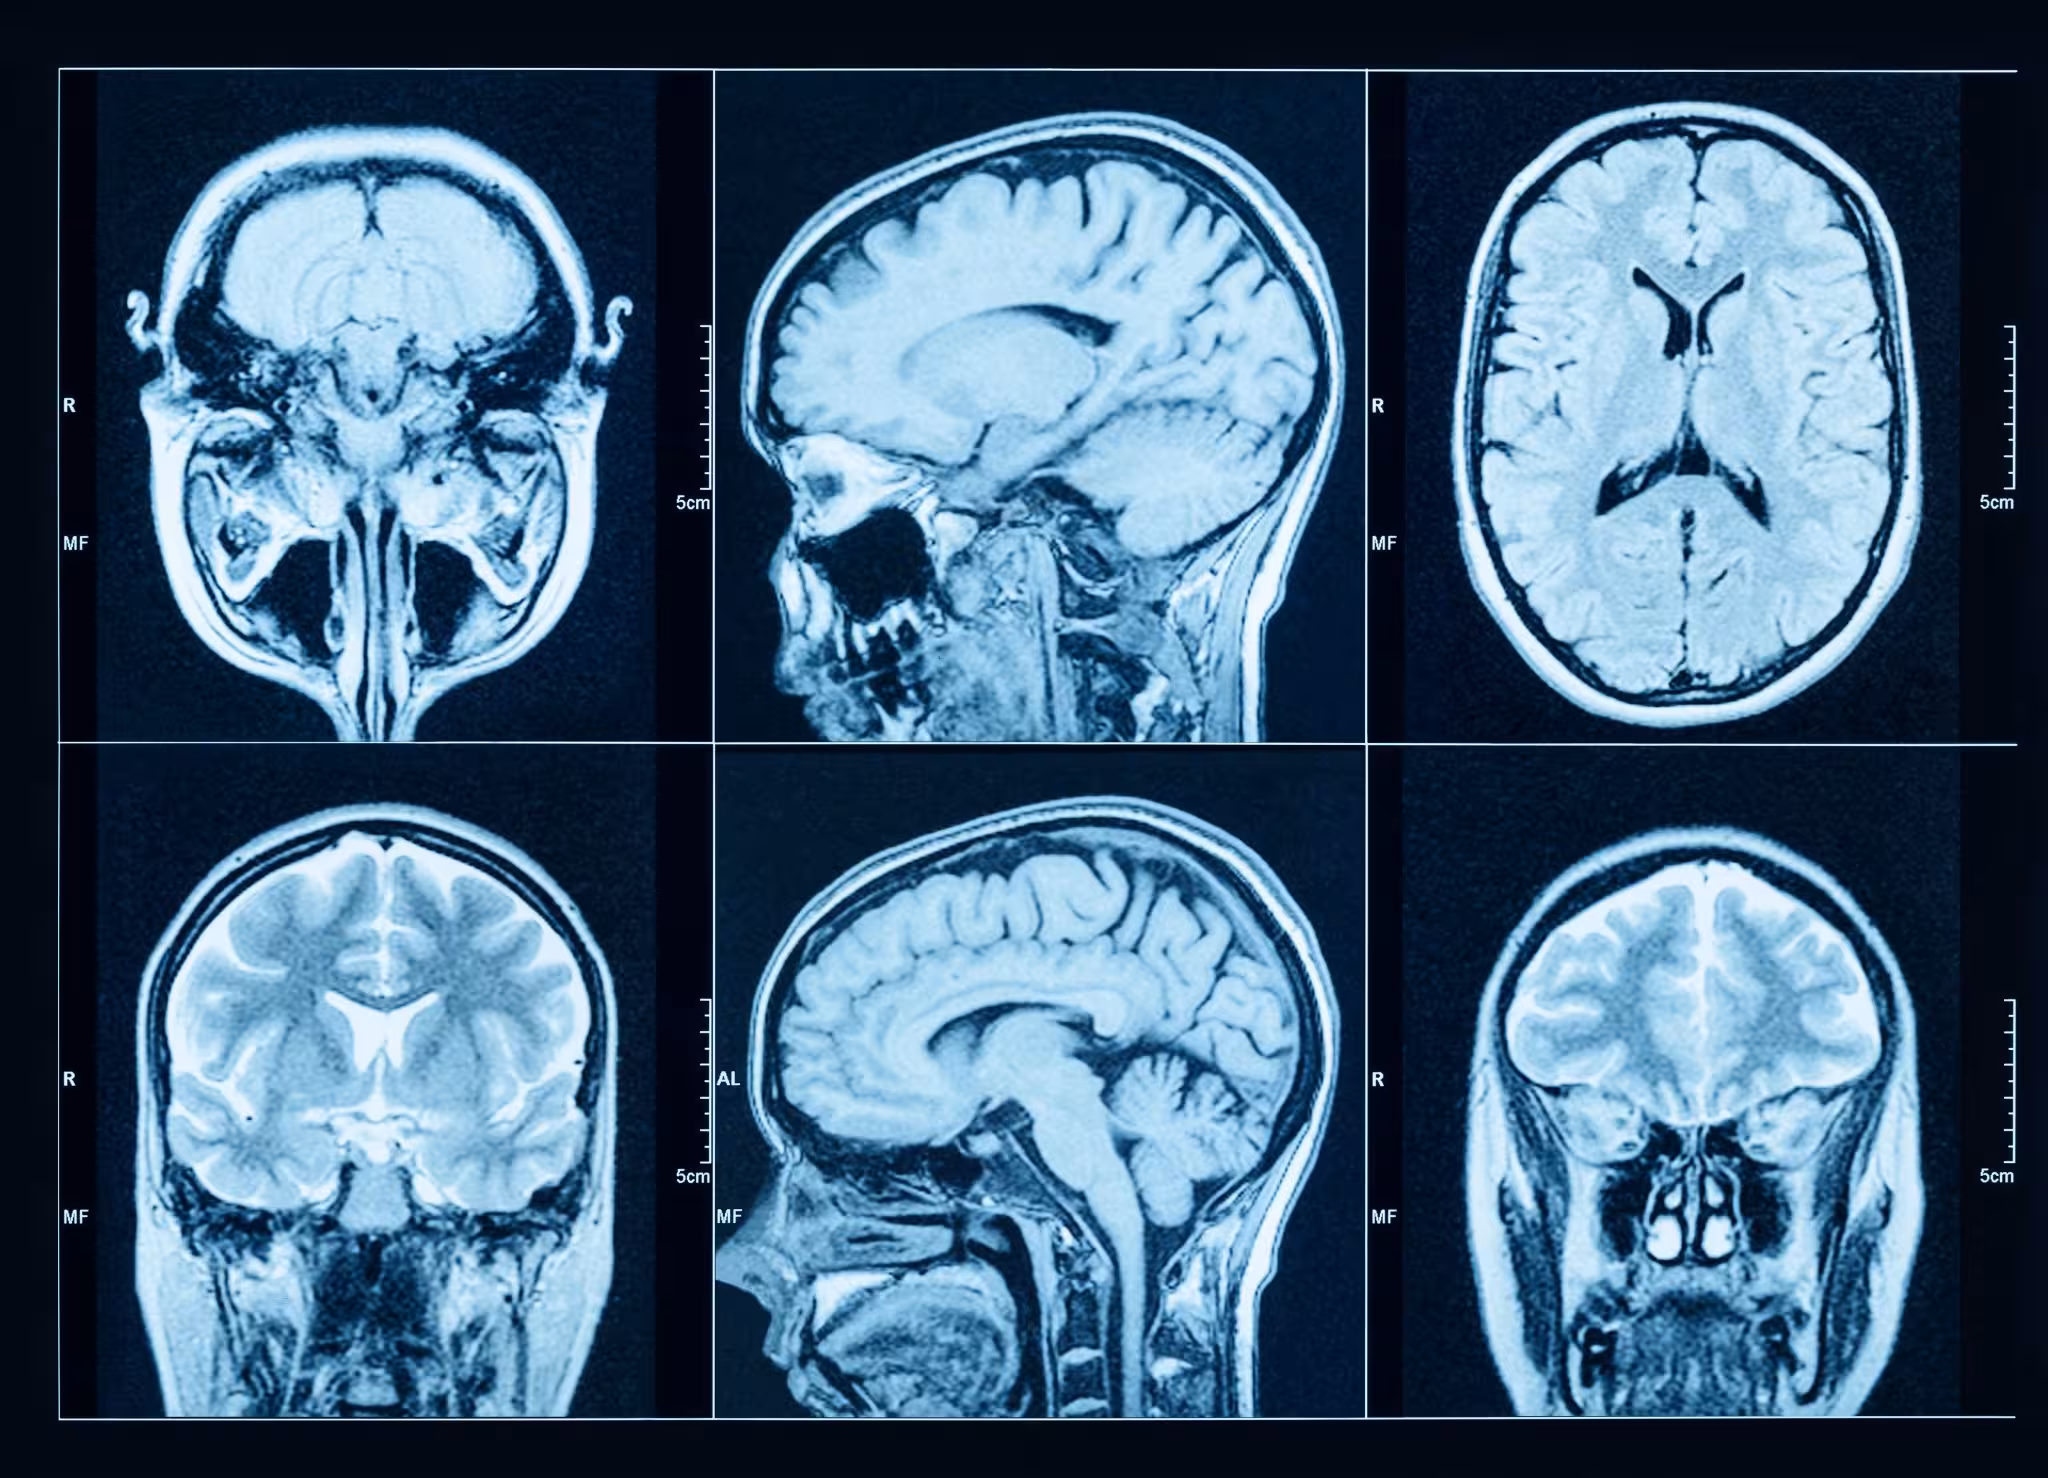

Everlab’s health scan imaging uses advanced, doctor-led diagnostics (including CTCA, Full Body MRI, and DEXA) to identify "silent" cardiovascular, metabolic, and structural risks before symptoms appear, allowing for a personalised, proactive longevity programme.

Investing in your long-term longevity requires precise, clinical-grade data. With comprehensive health scan imaging, you can proactively help identify cardiovascular, metabolic, or structural conditions that may otherwise go unnoticed until symptoms develop.

At Everlab, our advanced health scan imaging protocols are designed to provide a thorough picture of your physical health. By replacing uncertainty with objective diagnostic data, we help identify risks early, support your future wellbeing, and ensure you receive a personalised health protocol tailored to your unique biology.

True preventative care requires looking beneath the surface. The Everlab health scan imaging system uses clinical-grade diagnostic tools to map your internal biology. This lets us evaluate the critical systems that govern your daily performance and long-term longevity:

Cancer screening and full body imaging: We use a Full Body MRI, which uses a magnet and radio waves to create detailed internal body images, helping to identify abnormalities that may warrant further investigation. This is paired with an ultra-low radiation CT chest scan, which captures highly detailed images of your lungs without the need for contrast dye. This specialised low-dose CT scan (LDCT) is supported by the National Lung Screening Trial (NLST), which demonstrated a 20% reduction in lung cancer mortality among high-risk individuals screened with LDCT compared to chest radiography (NLST Research Team, NEJM 2011). It is designed to help identify early-stage lung cancer and other pulmonary conditions in at-risk individuals before symptoms appear, when clinical intervention may be most effective.